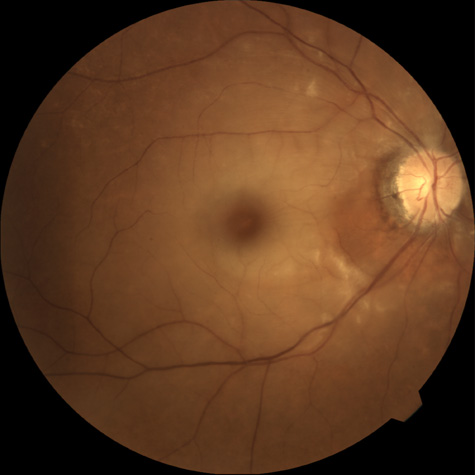

When a branch retinal artery is obstructed, there is usually whitening of the retina in the area supplied by the artery (Fig. 2). In most eyes (62% in one series), emboli are responsible for the obstruction.94 The temporal branch arteries are involved in almost all cases that have been reported,92,94 but whether this is because nasal branch retinal artery obstructions are rare or because such obstructions are simply asymptomatic is unknown. The characteristics of a branch retinal artery obstruction on intravenous fluorescein angiography are similar to those for central retinal artery obstruction.

Fig. 2. Multiple branch retinal artery obstructions in a young woman with encephalopathy and hearing loss. (Photograph courtesy of Jack W. Pierce, M.D.)